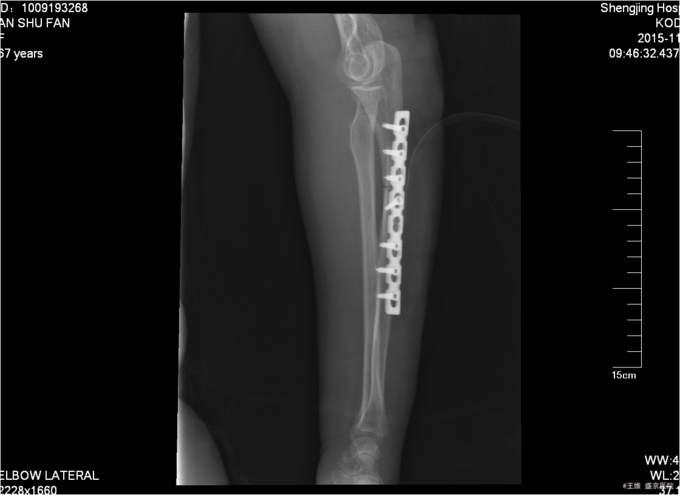

患者入院后完善相关检查,给予止痛,抗炎,消肿,冷敷等对症治疗后,择期全麻下行左尺骨骨折切开复位钢板内固定术。术后给予患肢抬高后,消炎,消肿等治疗,2天换药一次后,14天后拆线予以出院。